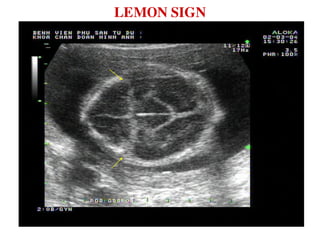

LEMON SIGN